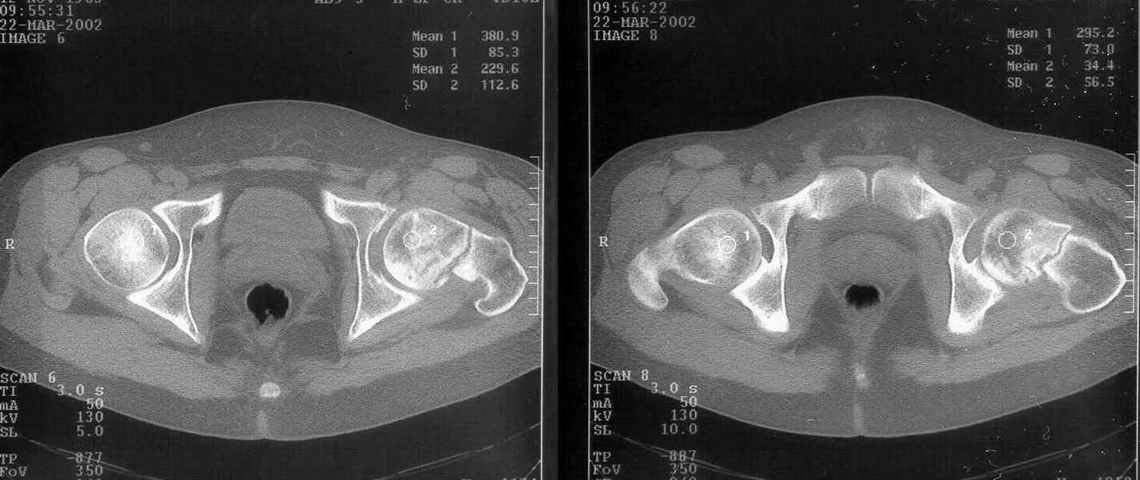

A miner 38 y.o. referred to us with 5 months old femoral neck lesion - after direct impact by a heavy construction he probably had non-displaced neck fracture. 3 months of spica cast, then non-weight-bearing. AP view and CT scan attached. Looks like AVN is present. ROM is painless and full, loading is also painless.